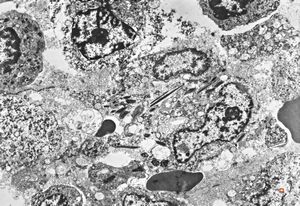

bone marrow - crystalloid inclusions Charcot-Leyden crystals formation

bone marrow - crystalloid inclusions Charcot-Leyden crystals formation v.s.